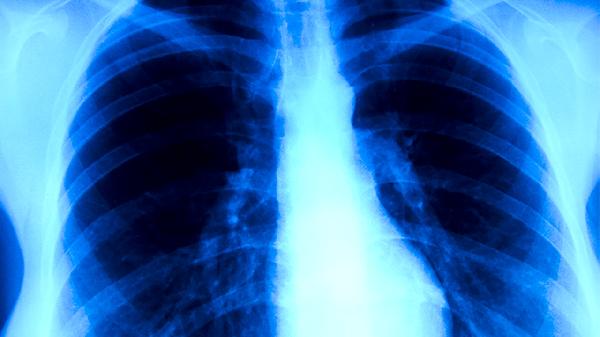

支气管肺炎在临床上常表现出一系列典型症状,包括咳嗽、发热、呼吸急促、胸痛以及肺部的异常声音。这些表现会随着病情的发展分为不同的阶段:早期、进展期和晚期。